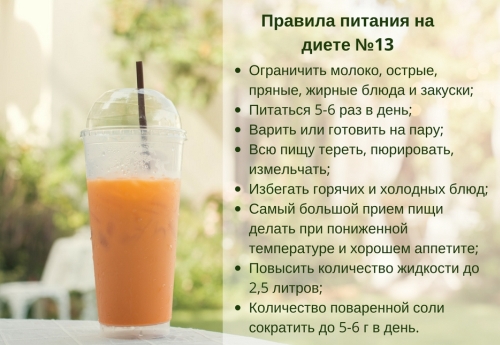

Еда для Легких и Бронхов - Полезные Рецепты